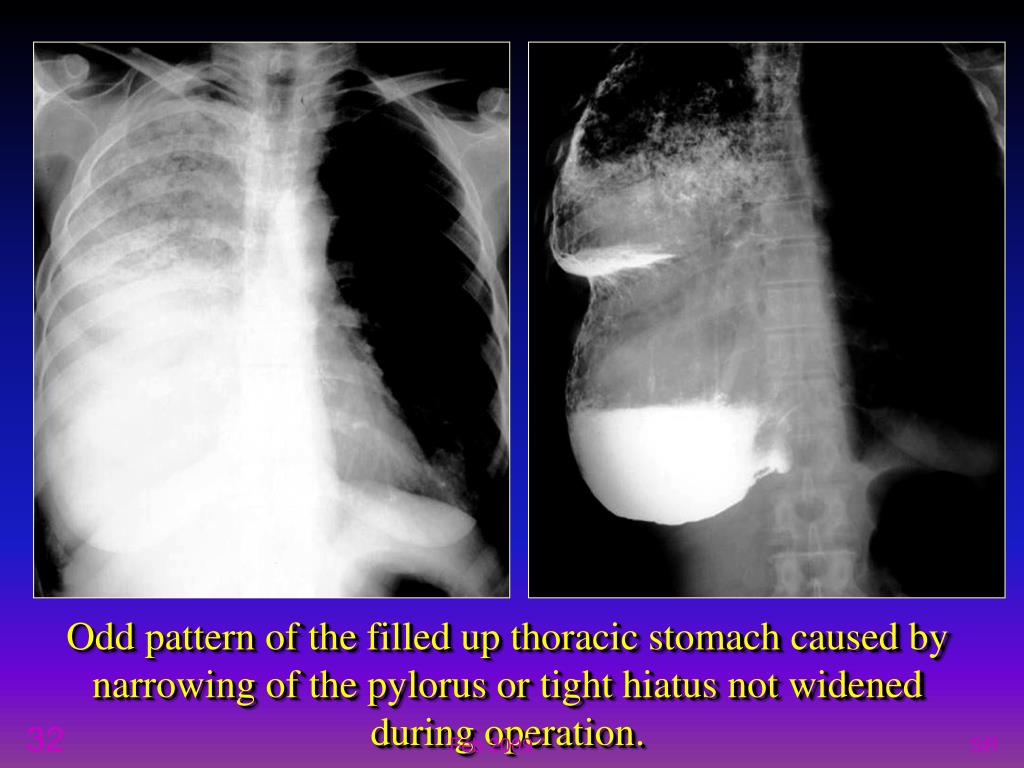

32. Odd pattern of the filled up thoracic stomach caused by narrowing of the pylorus or tight hiatus not widened during operation. SR